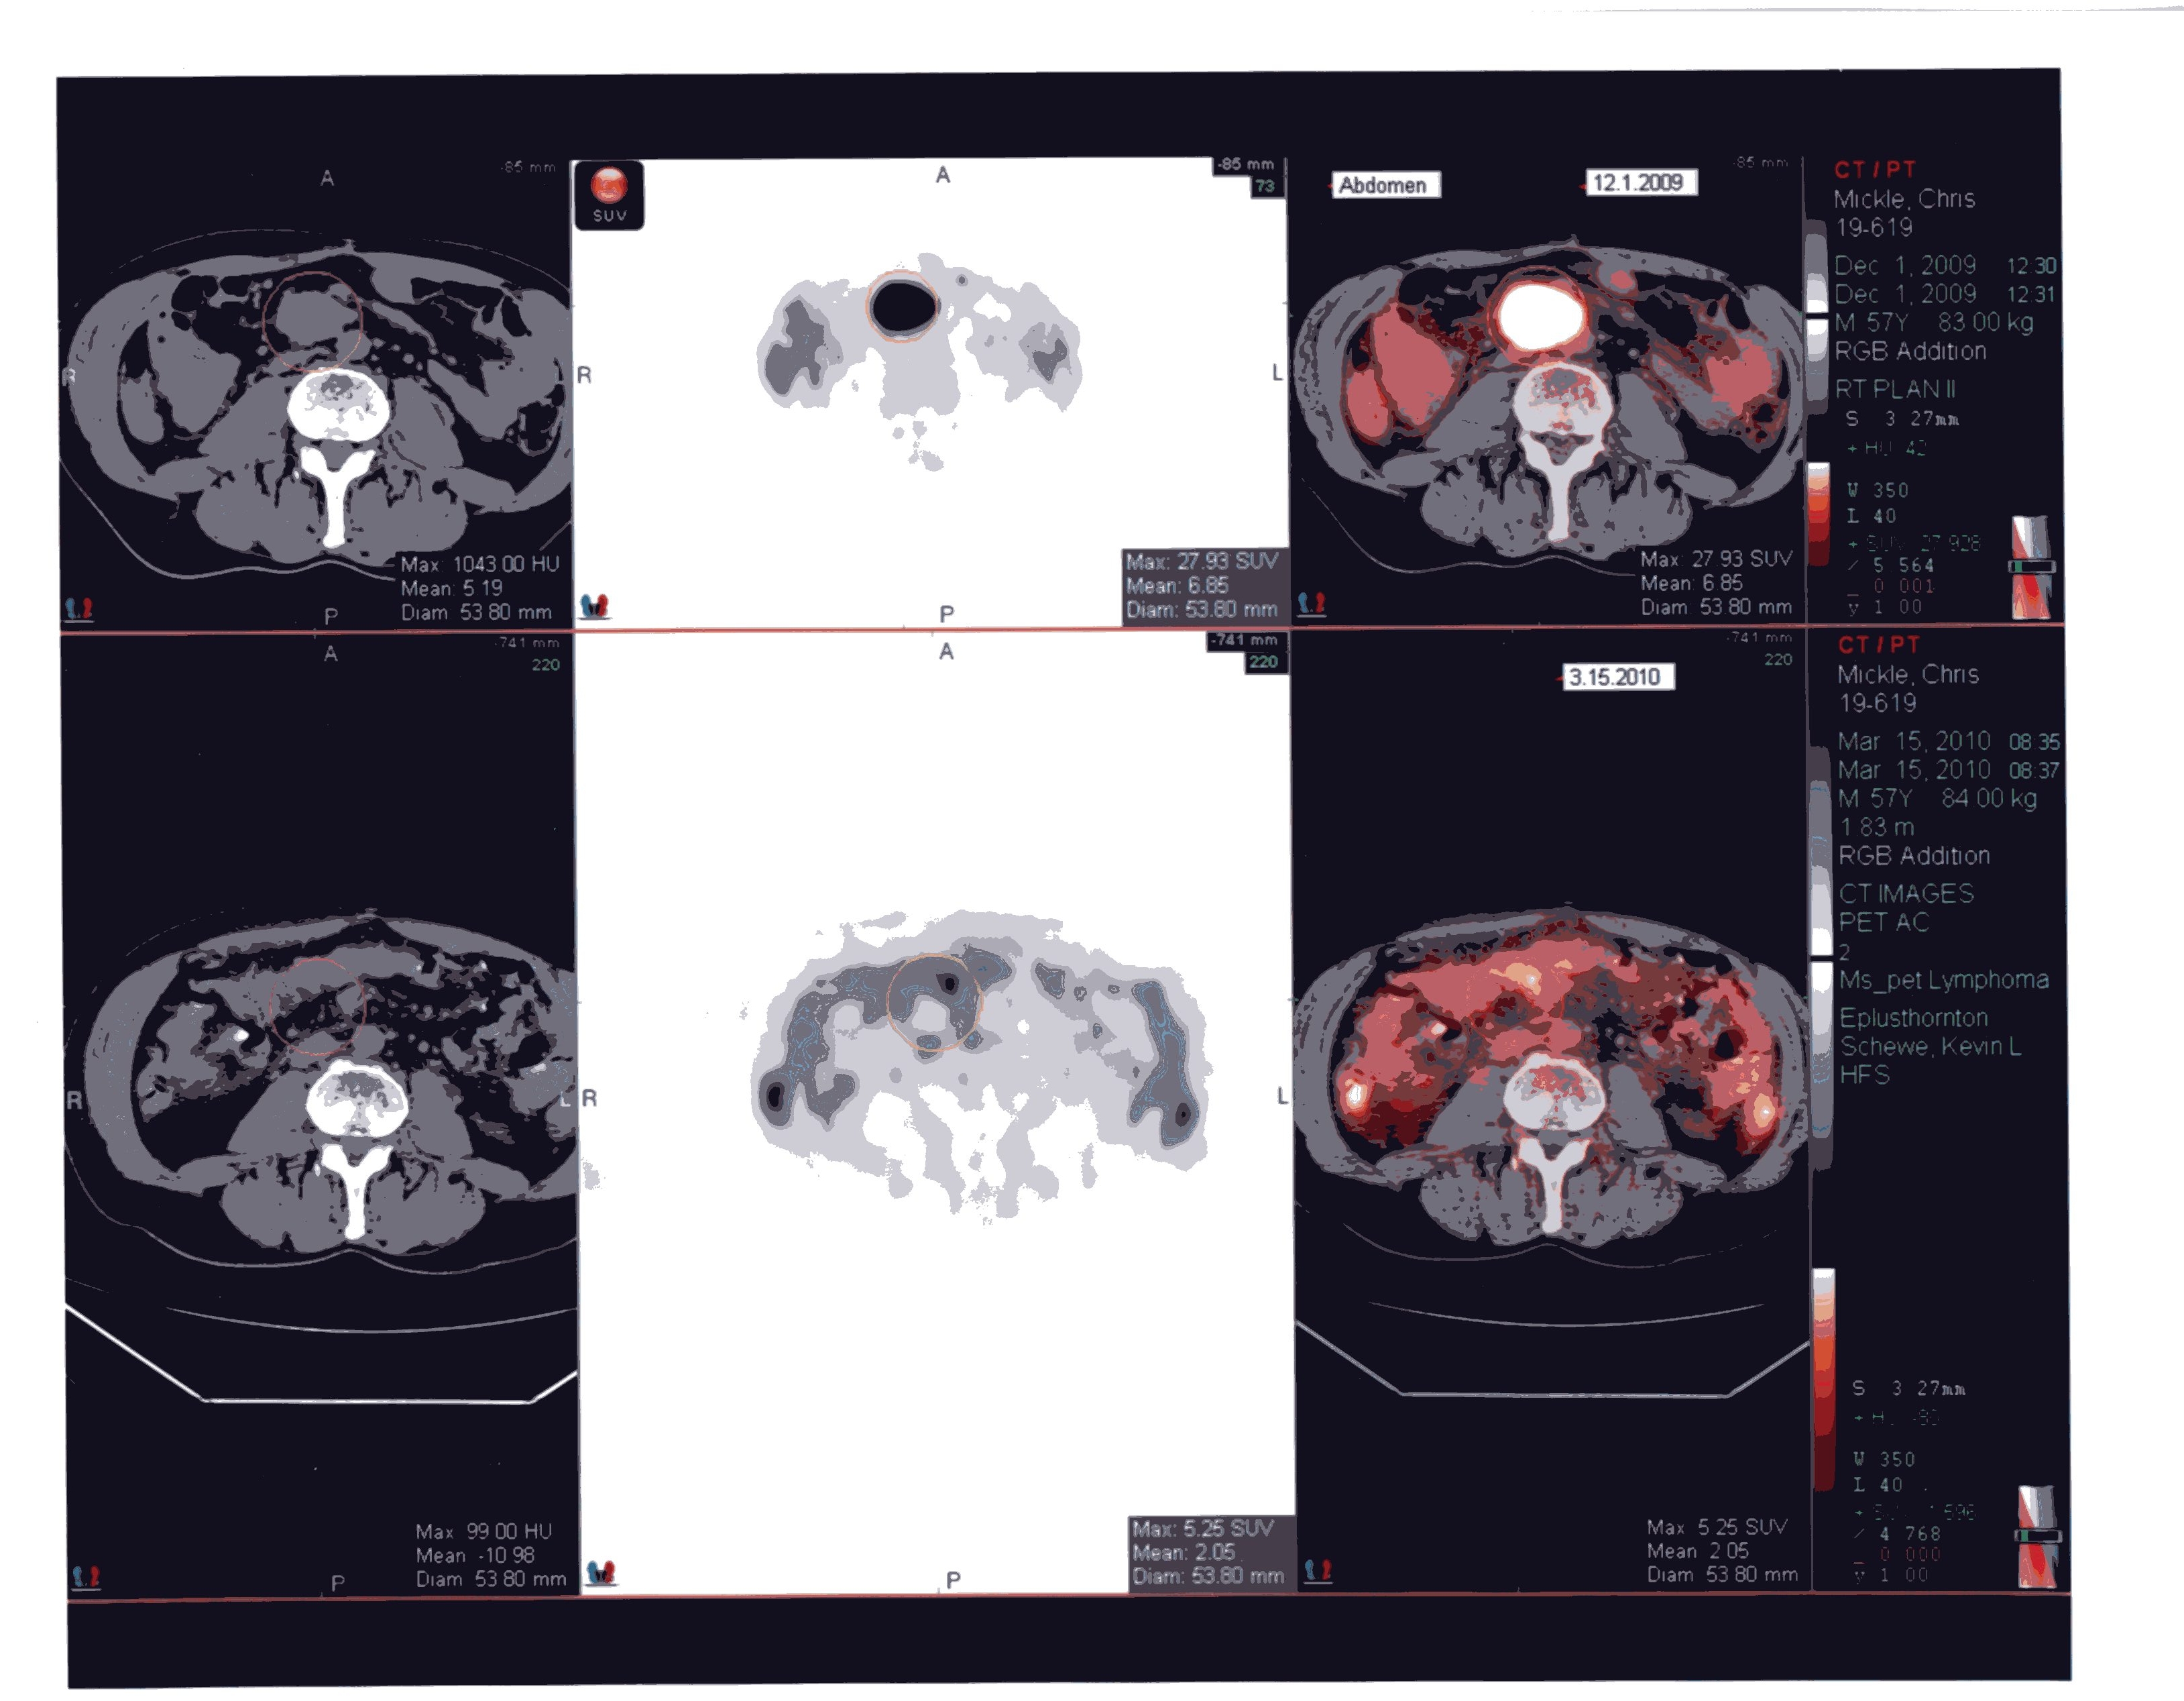

Tues 12/1/09 - It is hard to imagine that we'd be happy about seeing a tumor on one of Chris' PET scans. Well, not happy exactly, but it was a better report for a change. The scan did show one active and growing tumor in his abdomen. Same tumor that has been the most problem from the beginning. But the scan also showed that the tumors that were radiated early this year are no longer active and are shrinking. Chris' oncologist was excited enough about it that he immediately recommended radiation (hard for a "chemo" doctor to do sometimes). So, Chris starts radiation on Monday. Because of some radiation overlap from previous treatment, he will be getting low dose treatments twice a day.

Fri 3/19/2010 - Chris had a PET scan on Monday. On Wednesday we got the results and it was the best news we could have hoped for. The PET was clean!!!! The radiologist called the results amazing! For the time being, Chris is in remission. There will be another PET scan in about four months. That will be the nerve wracking one.

PET Image

Amazing!

The whole report is here, if you'd like to read it. I've also uploaded a larger version of the actual scan.